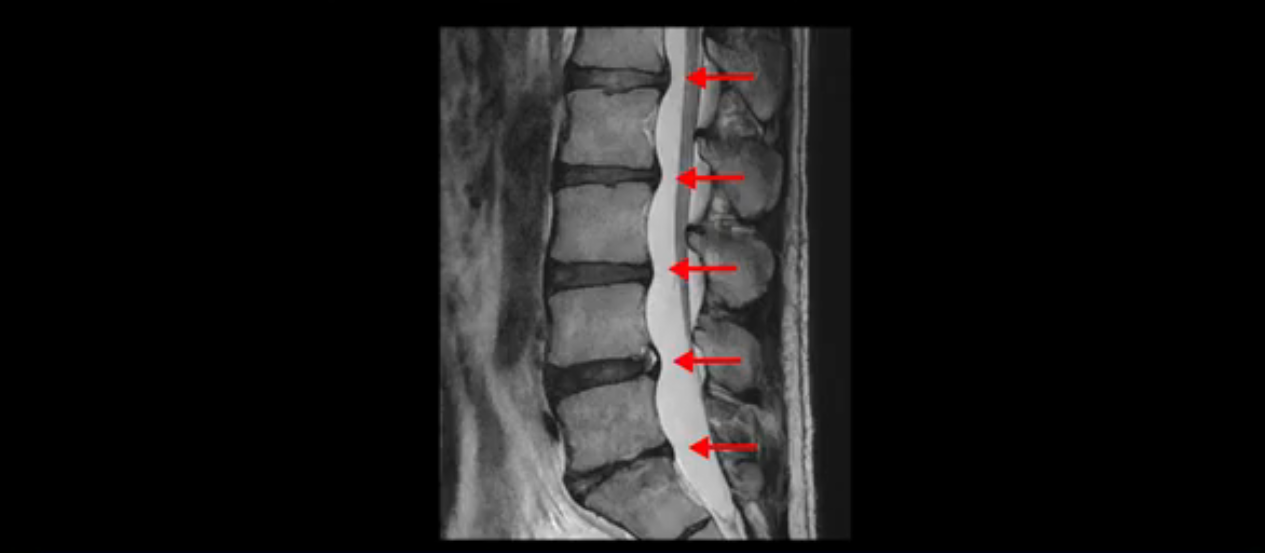

우선 이분 MRI를 보면 허리 모든 마디의 디스크가 퇴행되어 있고

여러 마디의 디스크가 조금씩 밀려나와 보이고, 디스크 섬유륜도 찢어져 보이는 마디도 보입니다.

그런데 이분의 증상과 MRI가 전혀 일치하지 않는데, 왜 그런지 지금부터 자세히 설명드립니다. 이분 증상은 앉으면 엉치와 허리가 심하게 아파 10분 이상 앉는 게 어렵고 양쪽 발가락이 앉아있을 때나 누워있을 때 다 저립니다. 걸을 때도 아파서 10분 걷기도 어렵습니다. MRI를 마디마디 살펴보면 1번 2번은 오른쪽으로 살짝 밀려나온 디스크가 있지만 전혀 심하지 않고, 뒤에 또 설명하겠지만 최근에 밀려나온 급성 디스크가 아니고 오래된 디스크로 판단됩니다.

2번 3번도 비교적 디스크 상태는 좋고 신경 구멍 넓이도 아주 넓습니다.

3번 4번도 마찬가지로 디스크상태 좋아 보이고 신경 눌림 전혀 없어 보입니다.

4번 5번은 가운데로 섬유륜이 찢어져서 디스크가 살짝 밀려나와 있지만 역시나 최근에 찢어지고 밀려나온 걸로 판단되지 않고 오래 전에 찢어진 흔적으로 보입니다.

5번 1번 역시 가운데로 디스크 조금 밀려 나와있지만 신경 공간 넓이는 아주 넓어서 신경 눌림 있을 거라고 예상이 안됩니다.

추간공도 보시다시피 왼쪽, 오른쪽 전부 다 매우 넓어서 신경이 눌릴만한 부분이 전혀 보이지 않습니다.